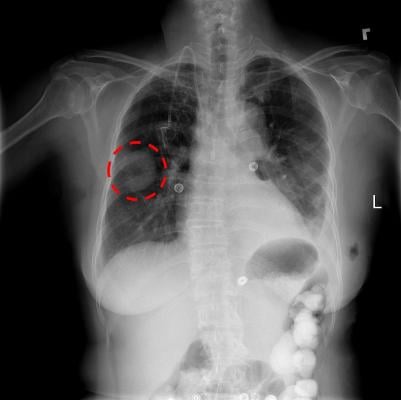

The partners began reviewing the use of artificial intelligence-enabled workflows in radiology with Agfa more than two years ago. Upon completion of phase one of onsite validation early January 2018, and on analysis of preliminary data, the algorithm was able to correctly identify lung diseases in chest X-rays approximately 90 percent of the time. Phase two results in March 2018 showed further improved sensitivity to 95 percent. Anonymized chest X-ray samples were provided by DHA to Agfa.

As part of this joint collaborative effort, Agfa in partnership with the VRVis Center for Virtual Reality and Visualization in Vienna, Austria, began developing machine learning-enabled detection of abnormal chest X-ray findings. The algorithm processed approximately 4,900 chest X-rays, and two DHA MFC radiologists reviewed the findings detected by the AI algorithm. The two radiologists provided feedback via an AI-enabled workflow if they agreed or disagreed with the algorithm findings.